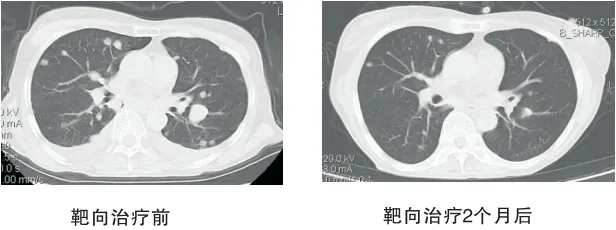

1、恶性肿瘤精准靶向治疗:肿瘤的分子靶向治疗是依据已知肿瘤发生中涉及的异常分子和基因,设计出针对这些特定分子和基因靶点的药物,通过药物干扰参与肿瘤细胞增殖分化所需要的分子,阻止肿瘤的生长和扩散。靶向治疗就像一颗颗精准发射的导弹,直击癌细胞;以肺癌为例,以前肺癌晚期平均生存时间只有10个月左右,现在通过靶向药治疗很多肺癌晚期患者生存期可以达到四五年实现长期生存。